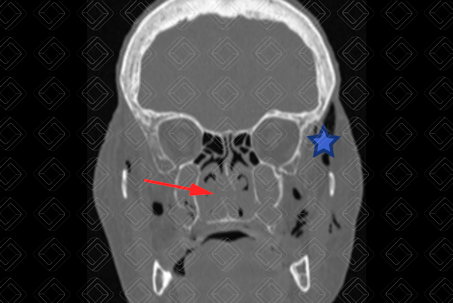

Texto alternativo para a imagem Créditos: Dra. Elazir Mota - Rio de Janeiro/RJ

Descrição das imagens: Tomografia computadorizada da face, cortes axial, coronal e reconstrução 3D. Múltiplas fraturas cominutivas e desalinhadas nos ossos nasais (setas vermelhas na primeira imagem) e septo nasal (seta vermelha na segunda imagem). Observa-se ainda o enfisema de partes moles decorrente do trauma (estrela).